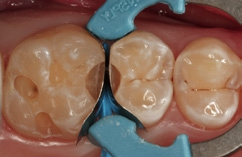

Bei der 55-jährigen Patientin imponierte eine okklusal penetrierte Sekundärkaries an dem Goldinlay an Zahn 15 (Abb. 8). Nach Aussage der Patientin war der Zahn seit ein paar Wochen aufbissempfindlich; die Vitalität war gegenüber Zahn 14 und 16 reduziert. Hieraus ergab sich die Behandlungsindikation zur Entfernung des Inlays und zur Vorbereitung einer endodontologischen Therapie. Nach der Entfernung des Inlays imponierte ein massiver Kariesbefall im gesamten Kavitätenbodenbereich (Abb. 9). Nach der Exkavation zeigten sich eine Verbindung zur Pulpa als auch diverse Infraktionslinien (Abb. 10). Die Verbindung zur Pulpa wurde interimsmäßig überkappt (TheraCal LC, Abb. 11); die Trepanation des Zahnes wurde dem Endodontologen überlassen. Vor einer endodontologischen Behandlung ist eine dichte adhäsive präendodontologische Aufbaufüllung essenziell. SDR flow+ hat die Indikation zur Aufbaufüllung in seinem Indikationsspektrum.

Der Aufbau eines solchen Zahnes mit einem Bulk-Flow-Komposit in zwei horizontalen Inkrementen (Kavitätentiefe deutlich > 4 mm) erleichtert und verkürzt selbst bei zwei Polymerisationszyklen die Gesamtversorgungsdauer im Vergleich zu einem dualhärtenden Aufbaukomposit. Hinzu kommt, dass alle dualhärtenden Aufbaukomposite keine definitiven Füllungsmaterialien sind und später entweder wieder entfernt oder komplett von einer indirekten Restauration eingefasst sein müssen. Das Bulk-Flow-Komposit hingegen ist ein definitives Füllungsmaterial, welches später – nach der endodontologischen Versorgung – als Kavitätenbodenelevation [16,23,31,34,47,60] verbleiben kann. Somit schont man mit Sicherheit Zahnhartsubstanz, wenn eine komplette Entfernung von Komposit gerade in den Tiefen des approximalen Kastens vermieden werden kann. Die Abbildung 12 zeigt den in zwei Inkrementen SDR flow+ in der Farbe A3 aufgebauten Zahn 15. Der Zahn ist so für den Endodontologen optimal vorbereitet. Die Abbildung 13 zeigt einen Ausschnitt aus der endodontologischen Diagnostik-Aufnahme und verdeutlicht die sehr gute Röntgenopazität sowie das sehr gute approximale Adaptationsverhalten.